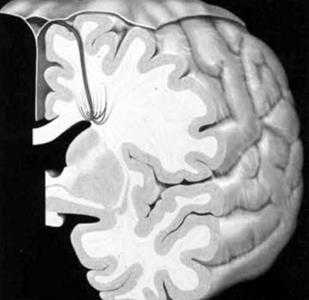

Венозная мальформация. Схема. Определяются мелкие расширенные венулы в виде «зонтика», «головы медузы», дренирующиеся в крупную транскортикальную вену, которая, в свою очередь впадает в верхний сагиттальный синус.

а) Т1 с внутривенным контрастированием. Стрелки показывают расширенные вены глубокого белого вещества, дренирующиеся в расширенную транскортикальную вену;

б) МР-венография с контрастированием показывает венозную дисплазию, дренирующуюся в расширенную внутреннюю мозговую вену. Венозная мальформация.